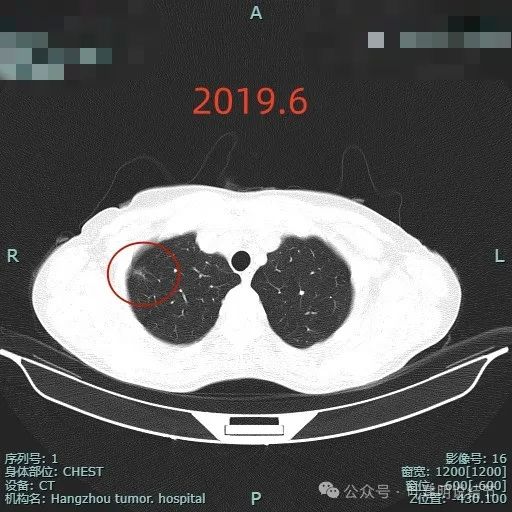

2019年时此处发展成为小片状磨玻璃影,似乎有点像斑片状,但灶内有少许密度略偏高的成分,也见到有微小血管走向病灶,此时若是对比来看,应该要考虑倾向肿瘤范畴的病灶了,当然风险仍低,仍可随访。